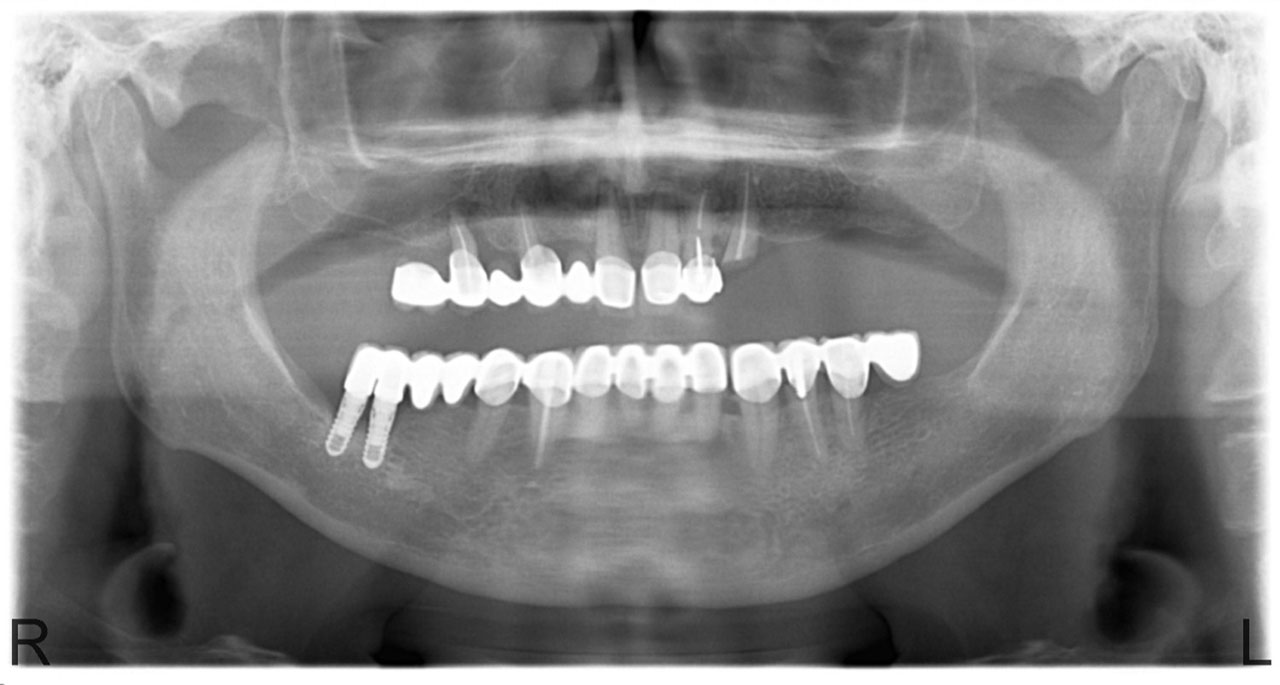

• esettanulmany-01

Implantáció előtt, gyulladt, törött fogak.

• esettanulmany-03

Imlantáció után,bal oldalon már a végleges hidakkal, jobb oldalon még csak az implantátumok.